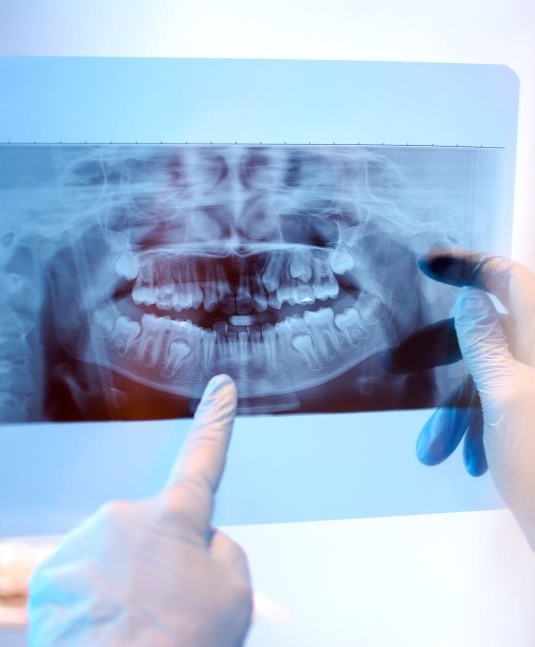

Wisdom Tooth Extractions

This is a surgical procedure that removes one or more wisdom teeth from your mouth. When wisdom teeth become impacted, they are stuck in your jawbone and gums and can cause pain and infection.